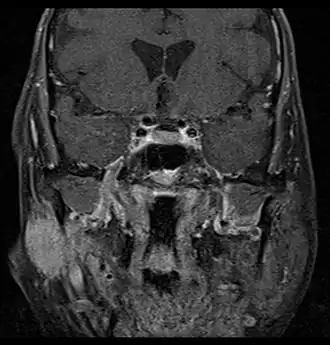

Coronal MRI showing right parotid adenoid cystic carcinoma with perineural spread of tumor: The tumor originates in the right parotid gland and spreads along the trigeminal nerve via the auricuotemporal branch extending intracranially through the foramen ovale at the skull base towards Meckel's cave. -

Primary treatment for this cancer, regardless of body site, is surgical removal with clean margins. This surgery can prove challenging in the head and neck region due to this tumor's tendency to show a perineural discontinuous growth, meaning that it follows nerves and different "nests" of the tumor can exist without a connection to the original tumor. Therefore, MRI-images should be analysed following nerve tracts up to the brainstem. Adjuvant or palliative radiotherapy is commonly given following surgery. For advanced major and minor salivary gland tumors that are inoperable, recurrent, or exhibit gross residual disease after surgery, fast neutron therapy is widely regarded as the most effective form of treatment.[13][14][15][16] Chemotherapy is used for metastatic disease. Chemotherapy is considered on a case-by-case basis, as data on the positive effects of chemotherapy are limited. Clinical studies are ongoing, however.